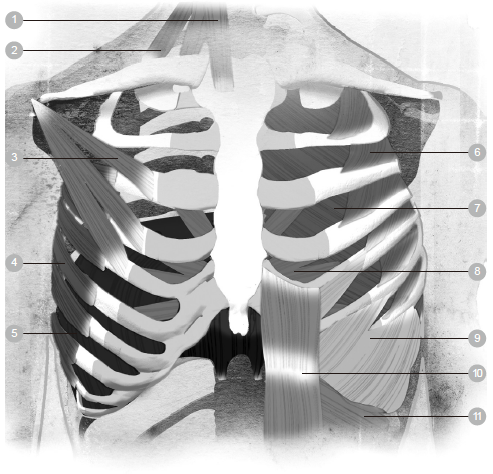

1 鼻子 6 肋间肌 11 气管

2 口 7 横膈膜 12 肺

3 会厌 8 鼻腔 13 支气管

4 胸膜 9 咽头(喉咙) 14 肺泡

5 肋骨 10 喉头

◆胸廓

胸廓的形状有如蜂窝,它包围、保护着体内最重要的维生器官—心脏和肺脏,并且使胸部的骨架保持稳定。胸廓几乎跟所有肋骨都互相连接,为每一根肋骨提供支撑力。人体总共有二十四根肋骨,每边各十二根,连接着身体背面的脊椎与正面的胸骨。肋骨和脊椎是借由胸椎关节串接起来,胸椎关节的巧妙设计让它可以随着每一次呼吸而自由活动。

有了这些可滑动的关节,整个胸廓便可以自在、轻松地活动。软骨把身体正面的肋骨结合在一起,这些软骨使得胸廓具有足够的强度,同时又富有弹性,可以顺应吸进来的空气多寡而适当地活动。人体的肋骨生来就具备弹性和可活动性,因为它们必须让内部的肺脏可以活动自如。

胸骨是一根长而扁的骨头,垂立在胸腔正面的中央,大约长十五公分、宽二.五公分,呈垂直状。它分为三个部分,功能是支持大多数的肋骨,并且保护气管不受伤害。上方的七根肋骨直接与胸骨相连,接下来的三根肋骨则是借由弧形的肋软骨,附着在胸骨上。剩下的二根肋骨称为漂浮肋骨,因为它们根本没有跟胸骨连接在一起,而是「漂浮」着,附着在身体背部的脊椎上。

当身体运作顺畅的时候,呼吸系统的肌肉和骨骼全部可以自由活动,彼此协调合作。如果身体内的肌肉过于紧绷,就会妨碍到直立、富有弹性,却又微妙平衡的骨架结构。这种肌肉紧绷会让胸腔周围的部位变得僵化,妨碍到呼吸系统天生的运作设计,使得原本毫不费力的呼吸动作变得大为吃力。

✘误解五:使用辅助呼吸肌有益健康

当呼吸系统是以天生自然的方式运作时,身体一点也不会感到费力,肺脏自会安静地充气、排气,根本不劳你动念去呼吸。然而,明明没必要,却刻意使用肌肉去呼吸的人,会把自己身上天生而来的呼吸活动破坏掉。他们认为,为了让足够的空气进入肺部,应该要用力呼吸才对。其实,这些人是在过度操用辅助呼吸肌,只不过这样的做法让他们感觉自己呼吸得比较深而已。

辅助肌主要分布于胸腔、脖子和肩膀,包括下面几种肌肉在内:

.斜角肌:作用是擡起最上方的两根肋骨。

.胸锁乳突肌:作用是擡起胸骨。

.斜方肌:作用是借由提起肩膀与肩胛骨而擡起胸廓。

.鼻翼:作用是张开鼻孔。

过度操用辅助肌的害处跟深度呼吸的害处非常相似。虽然我们可以过度操用这些肌肉来吸气、吐气,不过这种做法的唯一效果是促使人们养成浅呼吸的习惯。用这种方法呼吸的人,当横膈膜下降的时候,他们倾向于把胸腔往上擡;当横膈膜上升的时候,他们却把身体往下拉。这种呼吸法有时称为「反常呼吸」,因为它跟自然呼吸的运作方式恰好相反,会危害健康。

第二章曾经谈过,吸气的时候,横膈膜会下降,使肺脏内部呈现真空状态,让氧气进入,填满肺脏;吐气的时候,横膈膜会上升,形状有如一座圆顶体育场,把空气从肺脏压缩出去。接下来的练习可以帮助你厘清你的呼吸是正常或反常的。

1 胸锁乳突肌 5 横膈膜 9 外斜肌

2 斜角肌 6 肋间外肌 10 腹直肌

3 胸小肌 7 肋间内肌 11 内斜肌

4 前锯肌 8 胸横肌